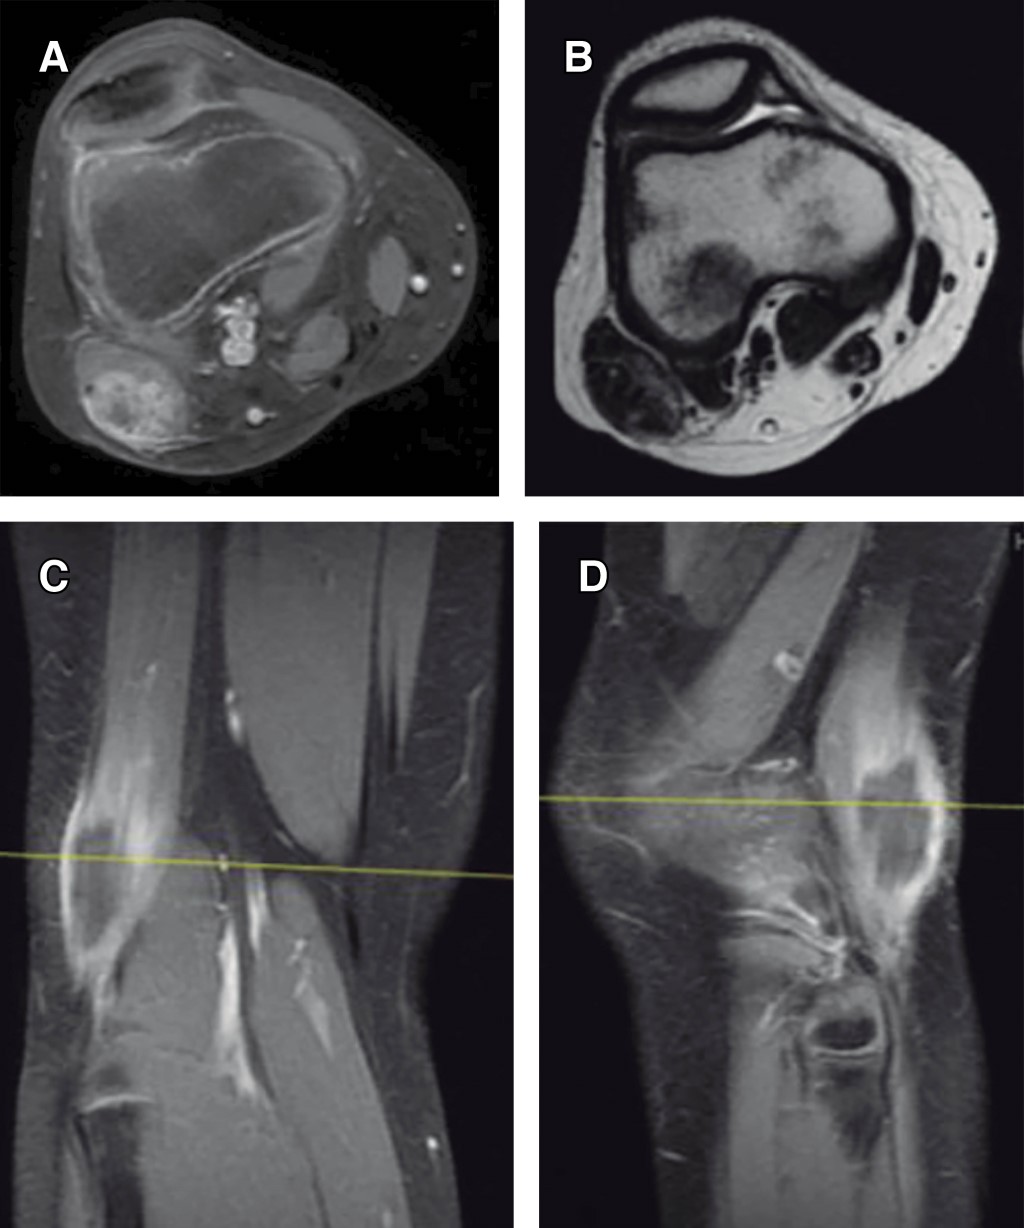

Myositis ossificans in children: a case series and literature review

Introduction: myositis ossificans (MO) is described as a non-neoplasic heterotopic bone formation at soft tissues and muscle. It is a rare entity in children, but it must be included within the differential diagnosis of a malignant tumor or an infection. Material and methods: the objective of this retrospective study is to describe three clinical cases of circumscribed myositis ossificans; the first one is a 10-year-old girl with a post-traumatic cervical injury, the second one is an 11-year-old boy with an atraumatic-type distal thigh injury, and the third one is an 8-year-old boy with a post-traumatic right thigh tumor. Results: the diagnosis was made on the basis of the clinical presentation, radiologic imaging and histopathological findings. The results obtained by conservative treatment were good in all cases, with resolution of pain and progressive reduction in size of lesions, without registering complications during follow-up. Conclusion: myositis ossificans is a rare entity, whose diagnosis is usually complex and may require a multidisciplinary team, and whose prognosis is nevertheless favorable.

Figure 3

Figure 4